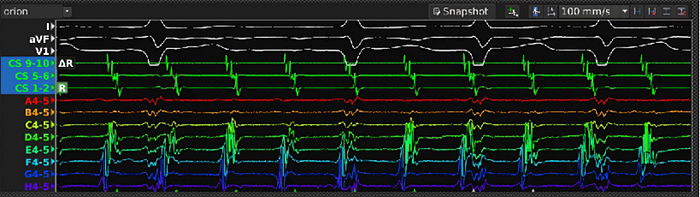

心航路医学自主研发的DePolar标测系统是目前全球首创的心脏“四维”标测系统,是与目前已经商业化的Carto/EnSite/Rhythmia/AcQMap等标测系统完全不同的下一代心脏标测系统。其最大特点在于,DePolar标测系统首次将磁电定位接触式标测和磁电定位非接触式标测在技术开发与临床应用层面都实现了无缝衔接,形成了统一的标测架构:

1.接触式标测系统,

是目前Carto/EnSite/Rhythmia等传统标测设备都采用的一种规则性的心律失常标测系统/方法。该系统在进行术中激动顺序标测时,通过人为设定一个腔内参考电极为时间零点,并根据心腔内标测导管

与心腔内壁接触

记录的心脏内腔电位(通常为双极电位)计算局部激动时间和参考电极时间零点的时间差(单位为毫秒ms)。手术医生通过移动标测导管在心腔内壁各个位置都采集心腔内电位,并利用参考电极把心腔内各个位置发生在不同心跳的局部电激动时间拼凑出全心腔的激动顺序图,从而了解规则性心律失常的传播路径。采用多电极的高密度标测导管和自动标测算法可以大大提高标测的密度和精度,同时缩短标测时间。

接触式标测系统的不足之处在于,它所获得的激动顺序图是一个拼凑出来的图,要获得这个图,患者必须处于一个规则性且稳定的心律失常状态,并且这种心律失常必须能够维持足够的时间,以便医生在心腔内各个位置进行记录电位。

因此,接触式标测系统只能标测室上速/房速/房扑/室早/室速等规则性心律失常。然而,对于房颤患者,在发病时其心腔内心律失常呈现不规则性,并且随时在发生变化,接触式标测系统对这种紊乱多变的心律失常就无能为力了。

2.非接触式标测系统,

是由Graydon Beatty博士率先提出的心律失常标测技术,特点在于使用独创的非接触式标测导管,并结合独家的

心电源标测算法

,在进行心律失常标测时,

无需与心腔内壁接触

,即可

即时

计算全心腔内的激动时间,从而实现对心律失常的

全心腔实时标测

。这也是全球唯一能够对非规则性心律失常,如房颤, 进行标测的技术。

通过将磁电定位接触式标测技术与磁电定位非接触式标测技术相结合,DePolar标测系统不但可以实现室上速、室速、房速等规则性心律失常的标测(磁电双定位接触式标测,与Carto/EnSite/Ryhthmia等传统标测系统功能一致),而且还可以实现房颤等非规则性心律失常的标测(磁电双定位非接触式标测,全球唯一),因此,它将是世界上第一个可以实现